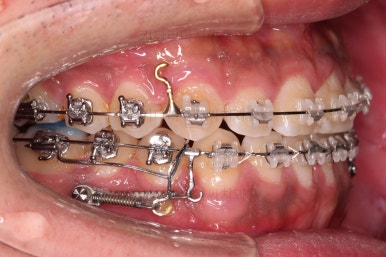

잇몸뼈에 미니스크류라고 하는 아주 작은 임플란트를 식립하고요.

미니스크류를 이용해서 뒤로 당겨주게 됩니다.

어느 정도 아랫니가 뒤로 와서 위아래의 교합이 맞춰졌다 생각들면 윗니도 함께 뒤로 당겨줍니다.

그래야 뻗쳐있던 앞니의 각도도 좋아지고, 코-입술 각도(비순각)도 좋아지기 때문이죠.

얼굴모습도 평가하여 목표치를 함께 의논해 가면서 결정합니다.